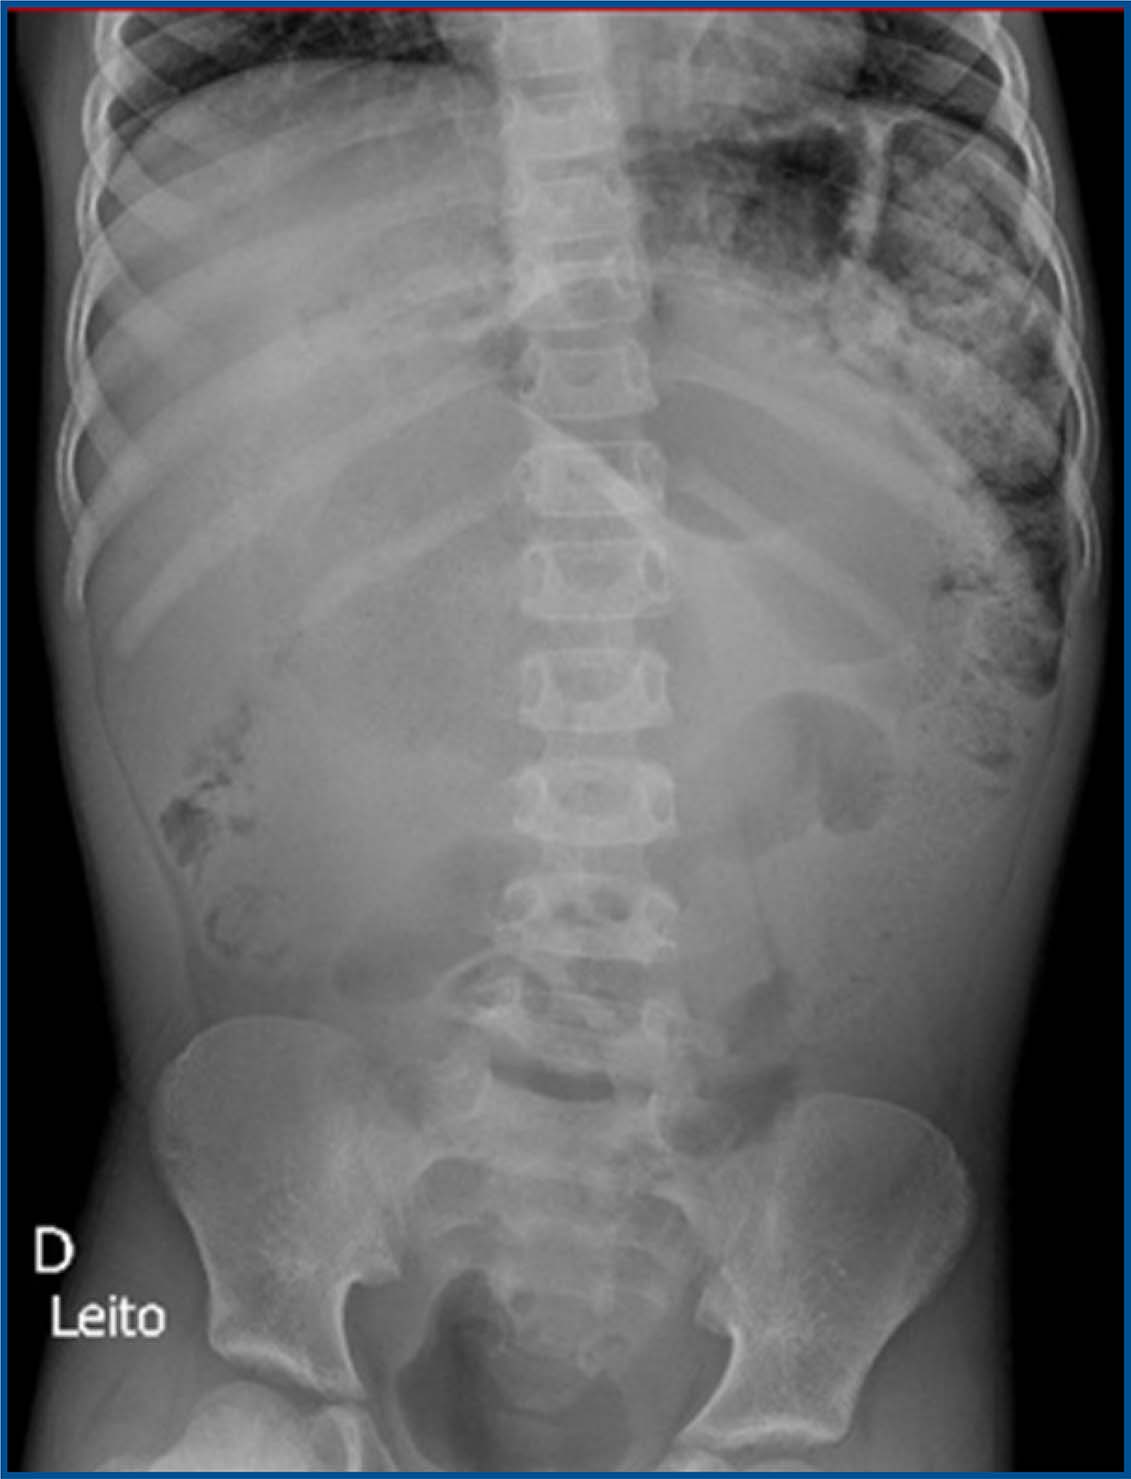

During the most recent outpatient visit, a significant fecal impaction was again identified, requiring surgical removal. Following the procedure, the patient remained hemodynamically stable, but experienced prostration, abdominal pain, poor oral intake tolerance, and diffuse abdominal tenderness on palpation, without signs of peritonitis. An abdominal X-ray was performed (figure 1), and the patient was started on a regimen of antibiotics, cessation of oral intake, basal maintenance fluids, and optimized analgesia.

Figure 1 : Abdominal X-ray with no evident abnormalities

Although hemodynamically stable, the patient continued to report intermittent abdominal pain. On physical examination, the abdomen was tense, with no rebound tenderness. Given these findings, a follow-up upright abdominal X-ray was ordered (figures 2 and 3), as the initial supine bedside X-ray showed no significant abnormalities.